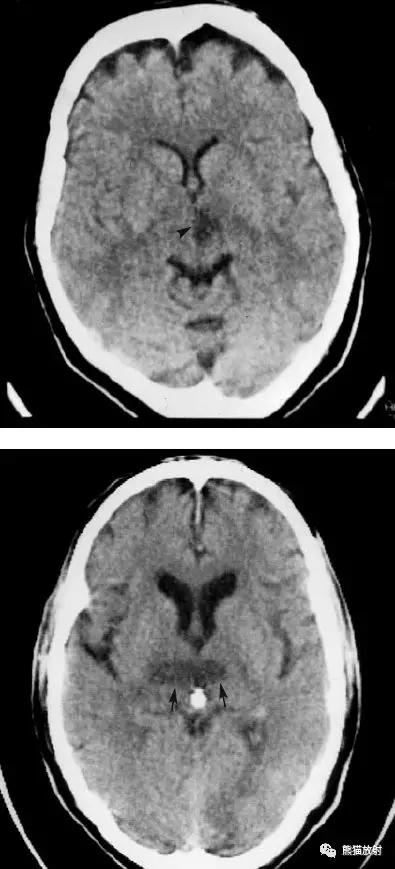

右侧豆状核梗死灶(发病后15d),明显均匀强化。另左侧丘脑见腔隙性梗死灶。

左侧额叶脑梗死(发病后12d),由于模糊效应平扫显示不清,增强扫描脑回样强化。

右侧基底节区脑梗死,增强后病灶看上去有所缩小。